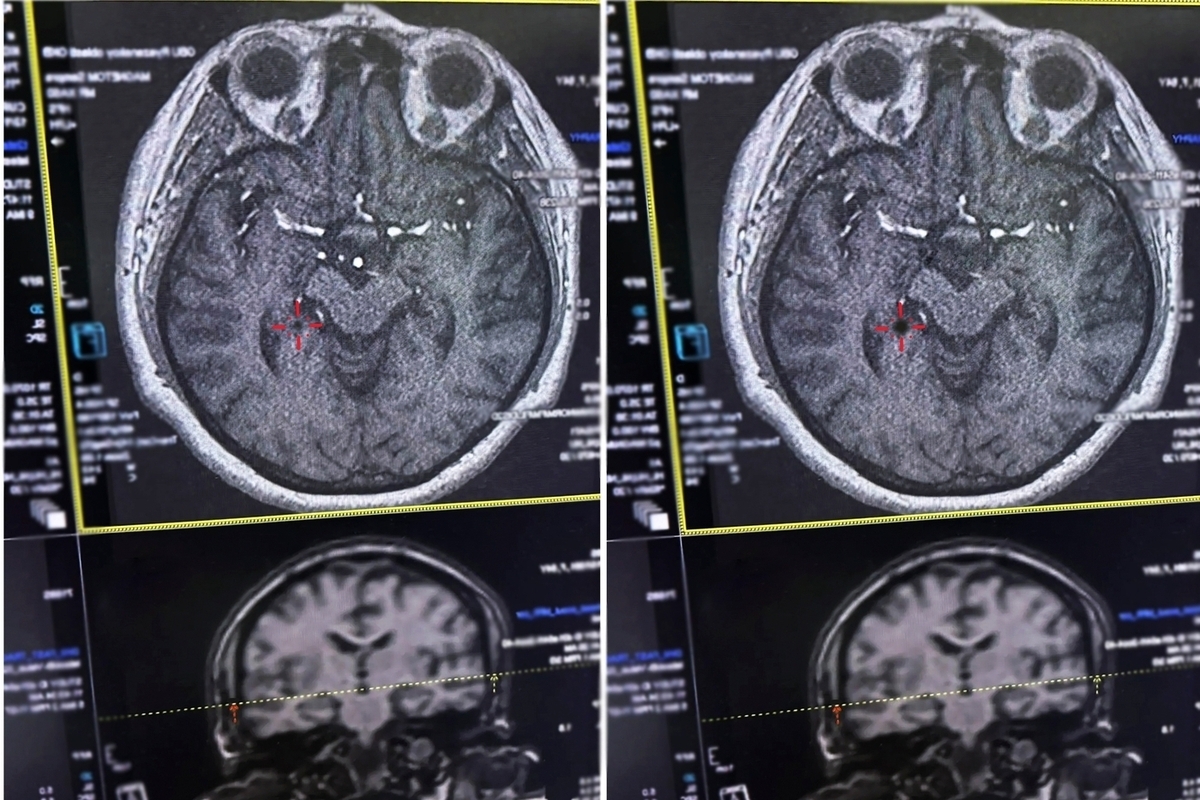

Фото минздрав Рязанской области

В Рязанской ОКБ спасли женщину с инсультом, рассказали в региональном минздраве.

Медики успели помочь пациентке в «терапевтическое окно» — критически важные первые 4,5 часа после начала инсульта.